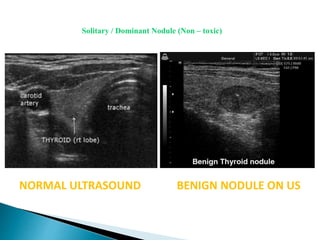

NORMAL ULTRASOUND BENIGN NODULE ON US

Solitary / Dominant Nodule (Non – toxic)